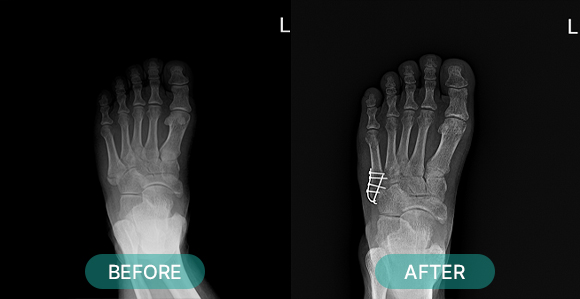

관혈적 정복이란 골절된 부위를 절개하고 뼈를 노출시켜 눈으로 직접 보면서 골절편을 정확하게 맞추는 방법으로 금속판과 나사 고정법, 핀고정법, 나사고정법, 골수 내정 고정법, 인공 관절 치환술, 외고정 기구 고정법 등등 여러 방식이 있습니다.

부위별 골절치료